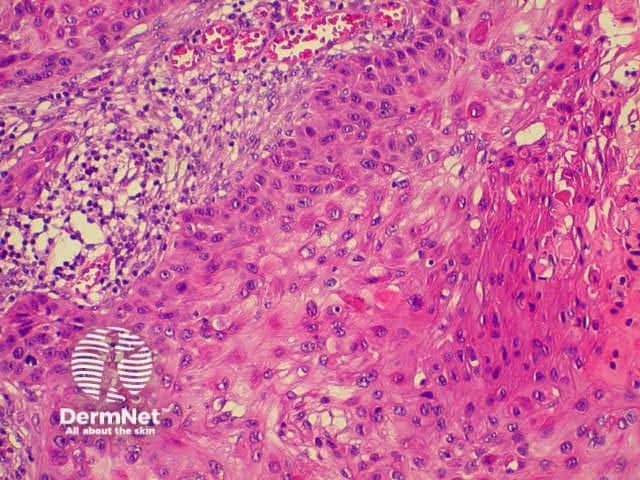

The histological characteristics of keratinocytic tumours are illustrated below.

Squamous cell carcinoma

SCC presents as an irregular keratinous nodule or a firm erythematous plaque, and frequently ulcerates. Histologically, atypical keratinocytes proliferate within the dermis.